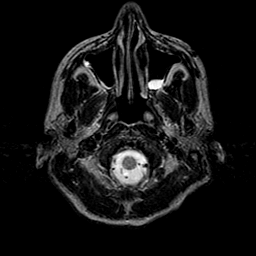

Sarcoma, MR Study #1 mr-t2 -- Slice #0